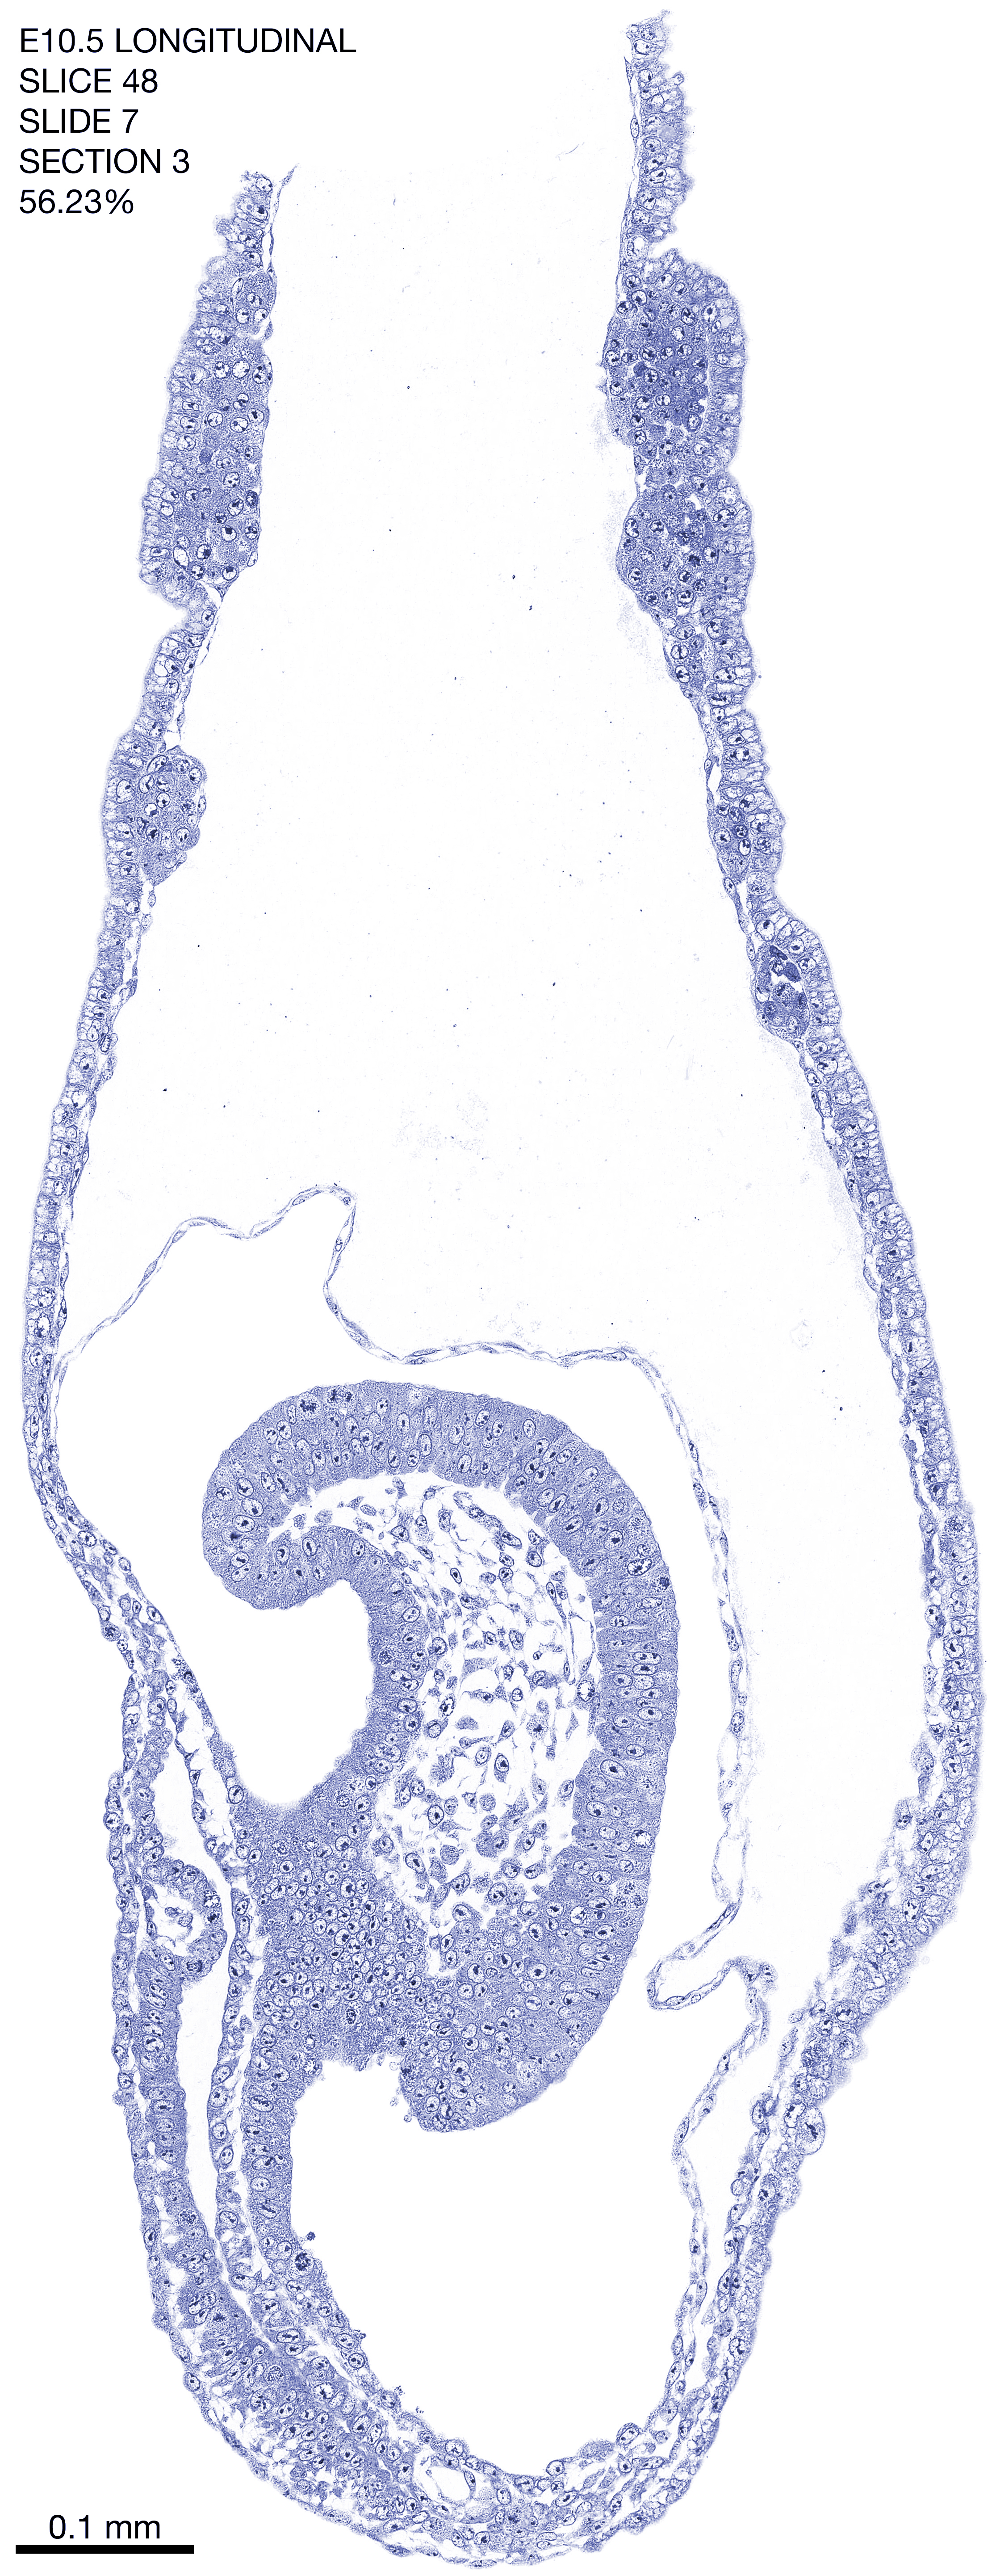

E10.5 Longitudianal Archive This page contains jpg files of ALL SLICES (each 3µm thick) that were scanned of the E10.5 longitudinally cut specimen. Download: Large | High Res Download: Large | High Res Download: Large | High Res Download: Large | High Res Download: Large | High Res Download: Large | High Res Download: Large | High Res Download: Large | High Res Download: Large | High Res Download: Large | High Res Download: Large | High Res Download: Large | High Res Download: Large | High Res Download: Large | High Res Download: Large | High Res Download: Large | High Res Download: Large | High Res Download: Large | High Res Download: Large | High Res Download: Large | High Res Download: Large | High Res Download: Large | High Res Download: Large | High Res Download: Large | High Res Download: Large | High Res Download: Large | High Res Download: Large | High Res Download: Large | High Res Download: Large | High Res Download: Large | High Res Download: Large | High Res Download: Large | High Res Download: Large | High Res Download: Large | High Res Download: Large | High Res Download: Large | High Res Download: Large | High Res Download: Large | High Res Download: Large | High Res Download: Large | High Res Download: Large | High Res Download: Large | High Res Download: Large | High Res Download: Large | High Res Download: Large | High Res Download: Large | High Res Download: Large | High Res Download: Large | High Res Download: Large | High Res Download: Large | High Res Download: Large | High Res Download: Large | High Res Download: Large | High Res Download: Large | High Res Download: Large | High Res Download: Large | High Res Download: Large | High Res Download: Large | High Res